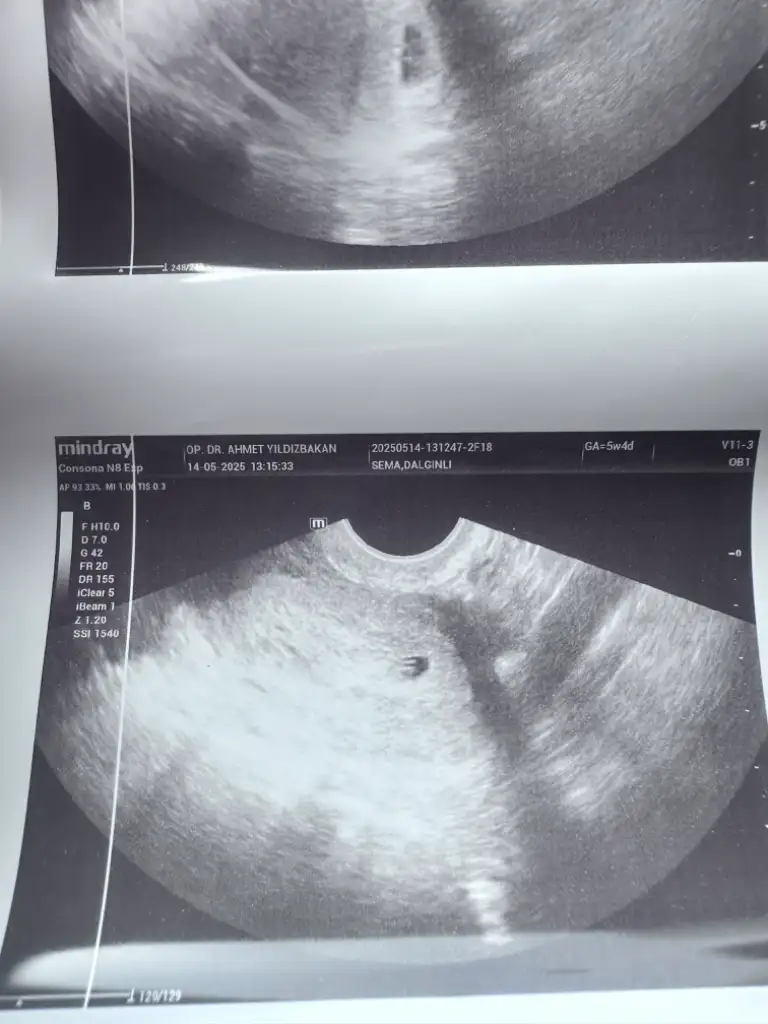

Kızlar keseme bakar mısınız normal mi 5+2 bugün doktor dedi bebek var içinde 10 gün sonra kalp atışına çağirdi

• IMG_3586.webp

IMG_3586.webp

31 KB · Görüntüleme: 25